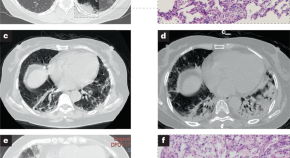

• In this Review, the authors provide an overview of what is known of the clinical features, pathogenesis and treatment of anti-melanoma differentiation-associated protein 5 antibody-positive dermatomyositis, including emerging biomarkers and clinical subtypes.

• Xin Lu

• Qinglin Peng

• Guochun Wang

Review Article